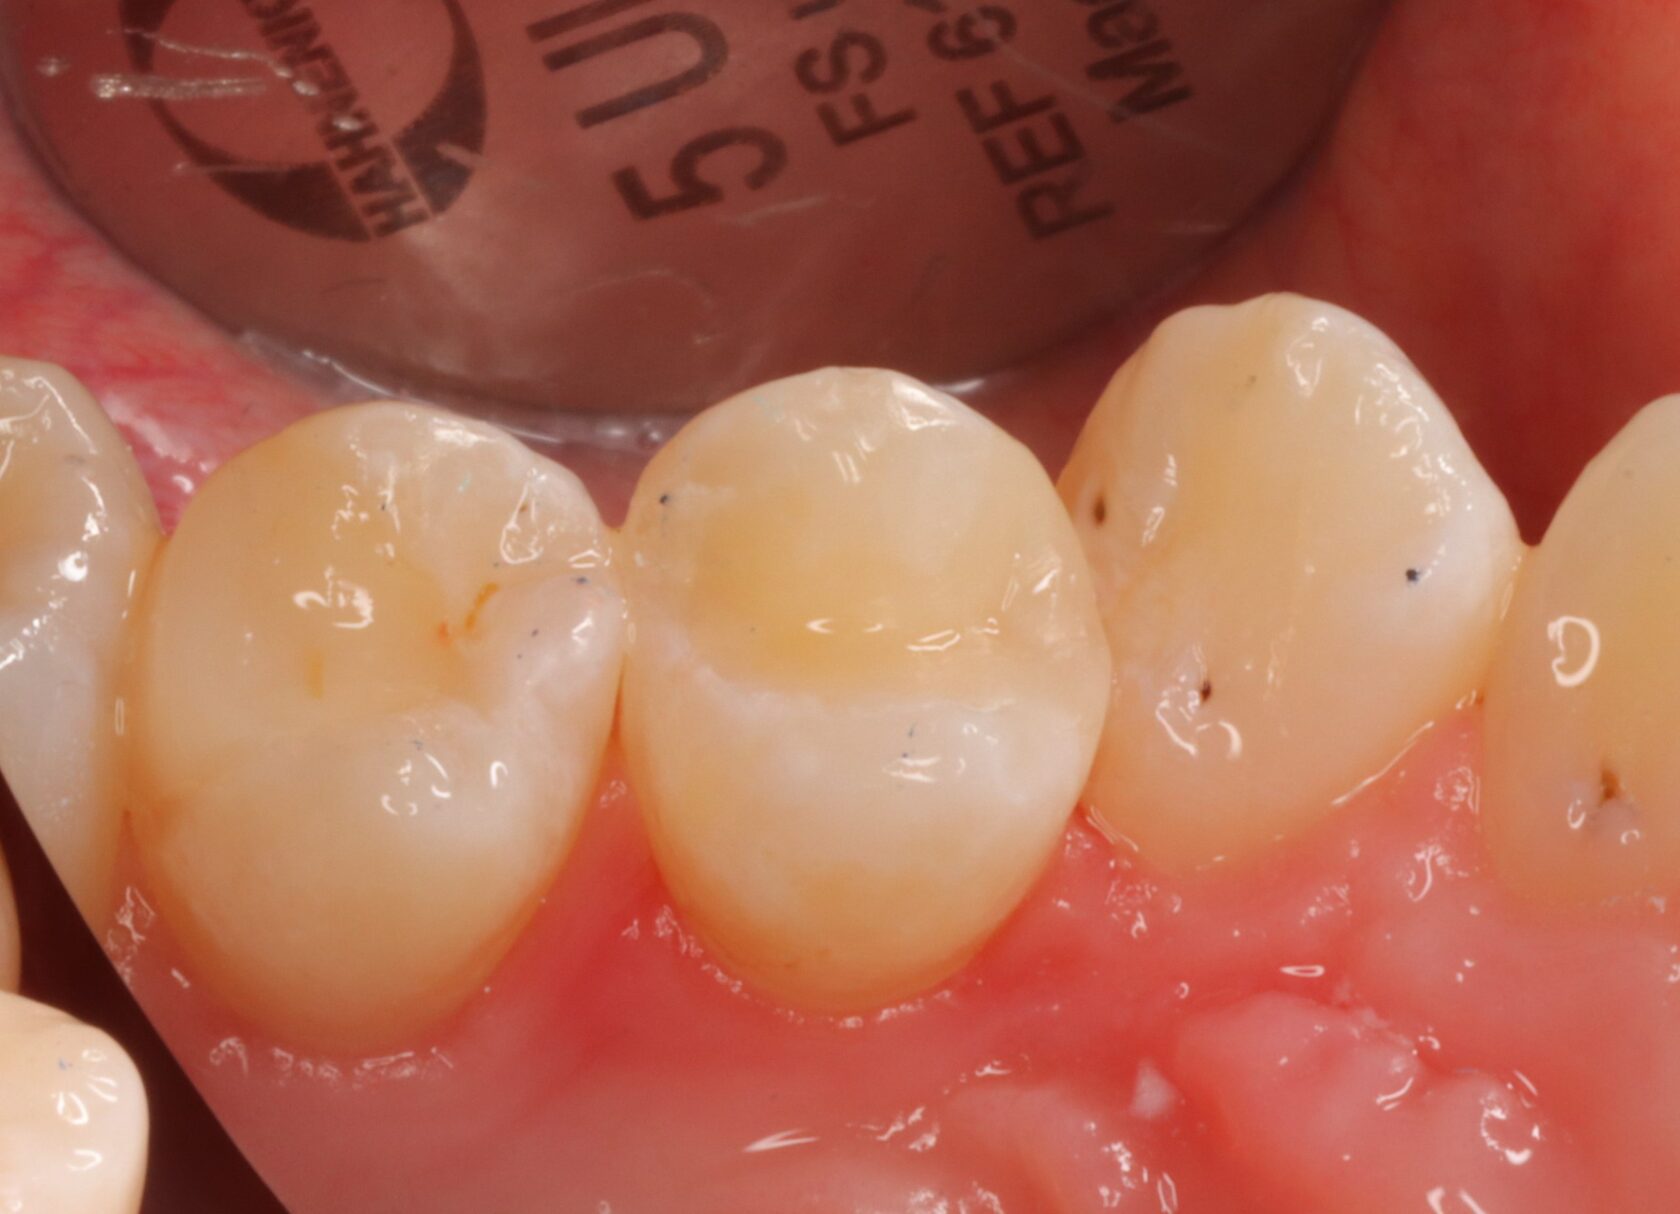

В итоге: кариес убран, стенка зуба заполирована, пациент обучен домашней межзубной гигиене.